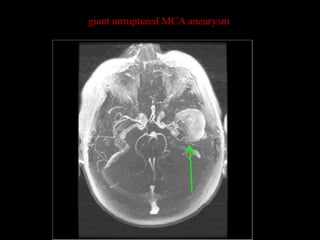

giant unruptured MCA aneurysm